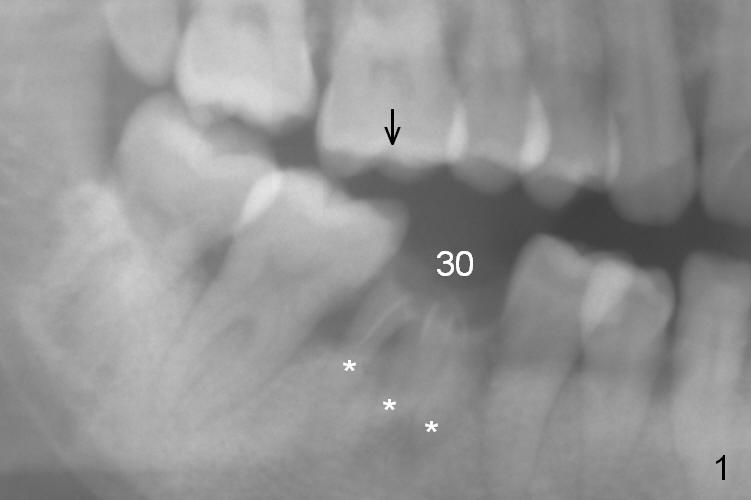

A 37-year-old woman is afraid of dentistry and procrastinates implant restoration at #30 (Fig.1). The opposing tooth is supraerupted (arrow) and warrants occlusal adjustment for #30 immediate provisional. Since there are 3 roots associated with #30 (*), the septum should be tripod, where osteotomy will be established after Clindamycin socket application. Primary stability of the immediate implant is further enhanced by the bone height. It is expected to gain ~ 6 mm in the native bone (Fig.2 blue line). As long as the osteotomy is slightly longer than the 2nd molar, there is minimal chance to involve the superior border of the Inferior Alveolar Canal (red dashed line). Magic Split and Expanders are to be used in combination with drills if necessary. Photograph the septum before and after osteotomy.

The 2nd method of osteotomy is to use 3.8 or 4.3 mm drill (after marking drill) in the middle of the septum at the depth determined by preop PA after removal of the coronal portion of the residual roots with high speed handpiece. Keep the drill in place for intraop PA. Remove the roots. A 4.5x13 mm implant will be placed. Either way, prepare PRF.